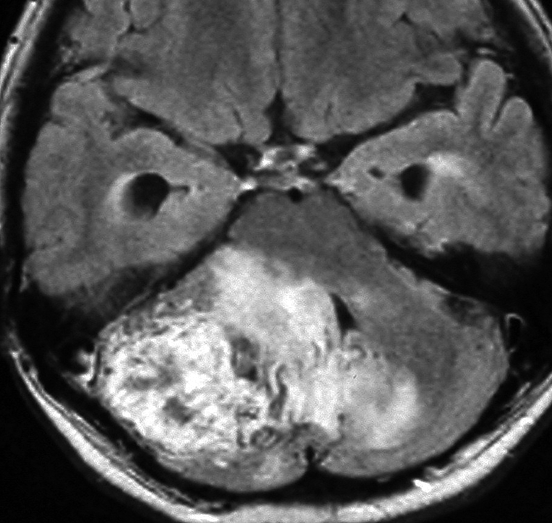

ものすごく難しい血管芽腫

これも血管芽腫です。おそらく小脳発生なのでしょうが,延髄の両側に強く癒着していて延髄の血管も腫瘍の中に入っていて,腫瘍血管には動脈瘤も合併していて破裂しました。この腫瘍を摘出するのは不可能にも思えましたが,無事にできました(下の写真)。患者さんも私もへとへとになりました。 でも,このような血管芽腫の手術はうまく行くとは限りません,手術不可能と考えた方がいいかもしれないと今でも思っています。手術すると決めればものすごく高いリスクを患者さんも外科医も背負うことになります。放射線治療をして治るサイズではないので他に治療法はありませんが (>_<) 大きな血管芽腫を手術する提案をされたら,少なくとも執刀医の経験数は尋ねましょう。

フォンヒッペルリンドウ病に合併した大きな右小脳半球血管芽腫です。大きなものでは静脈環流障害(鬱滞)のために脳浮腫を来すことが多いし,その分,手術時の静脈圧が高くて止血が難しいと考えなければなりません。水頭症を呈して症状は重篤でしたが,右後頭窩開頭で比較的簡単に全摘出できて回復しました。小脳半球に生じるものは手術で大きな障害を残すことはほとんどなく術後の症状症状の回復も順調なことが多いです。